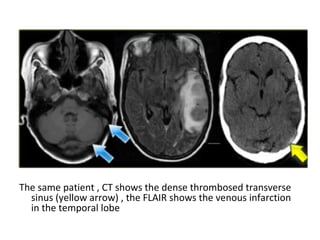

foramen of Monro

1 superior sagittal sinus

2 inferior sagittal sinus

(a) FLAIR shows the venous infarction in the temporal lobe , (b) CT nicely

demonstrates the dense thrombosed transverse sinus (yellow arrow)